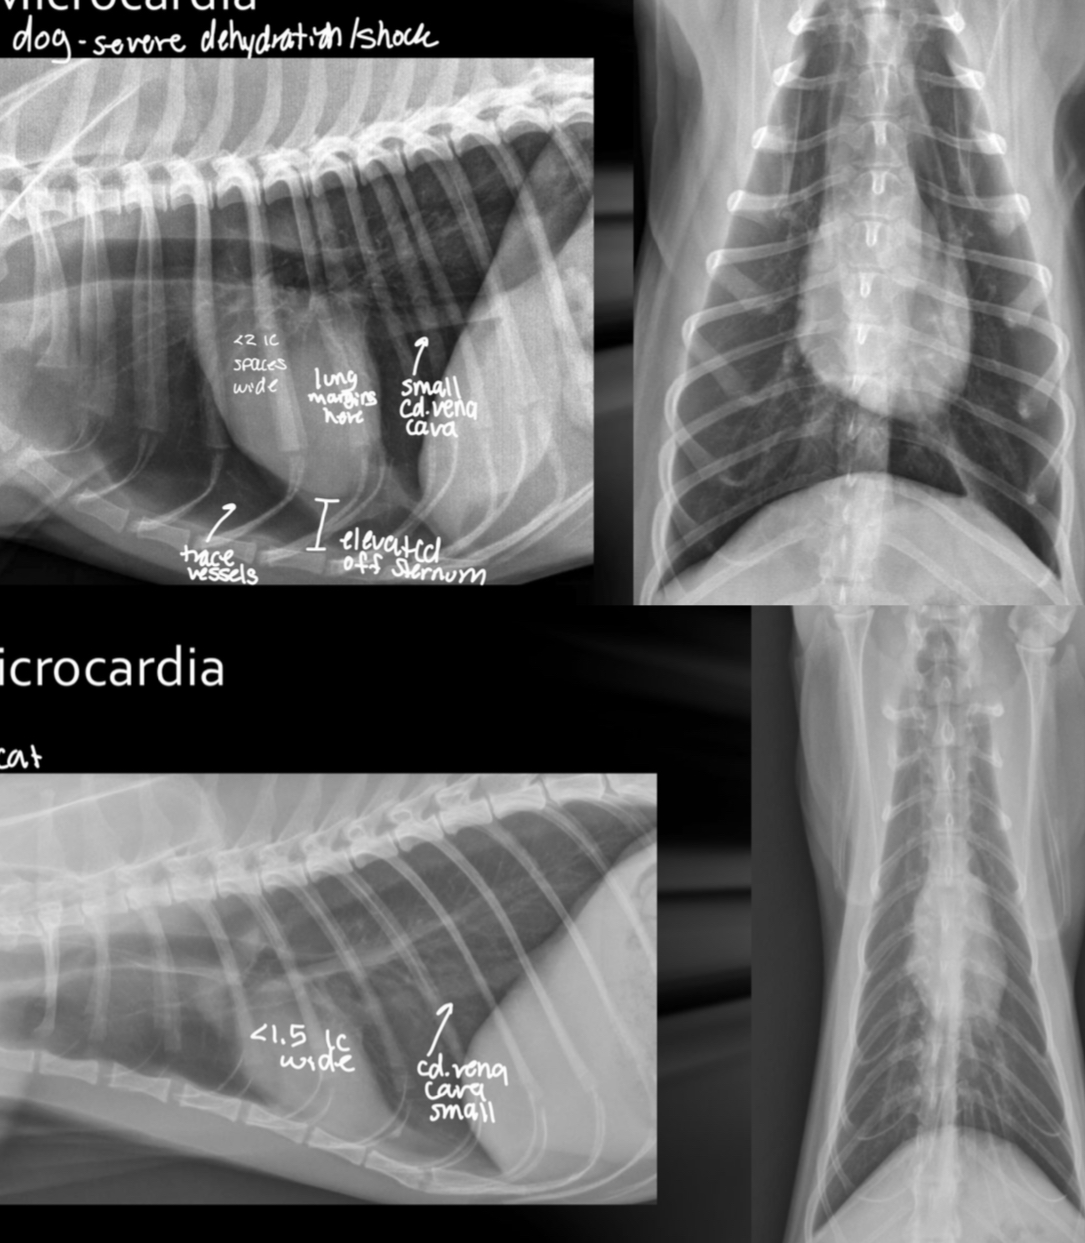

Microcardia cause

Dehydration, shock, Addisons (electrolyte imbalance)

Microcardia roentgen signs

-small cardiac silhouette (<2 IC in dog, <1.5 IC in cat)

-pulmonary hypoperfusion (small vessels)

-consistently small CdVC

-lung margins visible

-heart elevated off sternum

-still can trace vessels

What is going on with this dog heart?

Microcardia

What is going on with this cat heart?